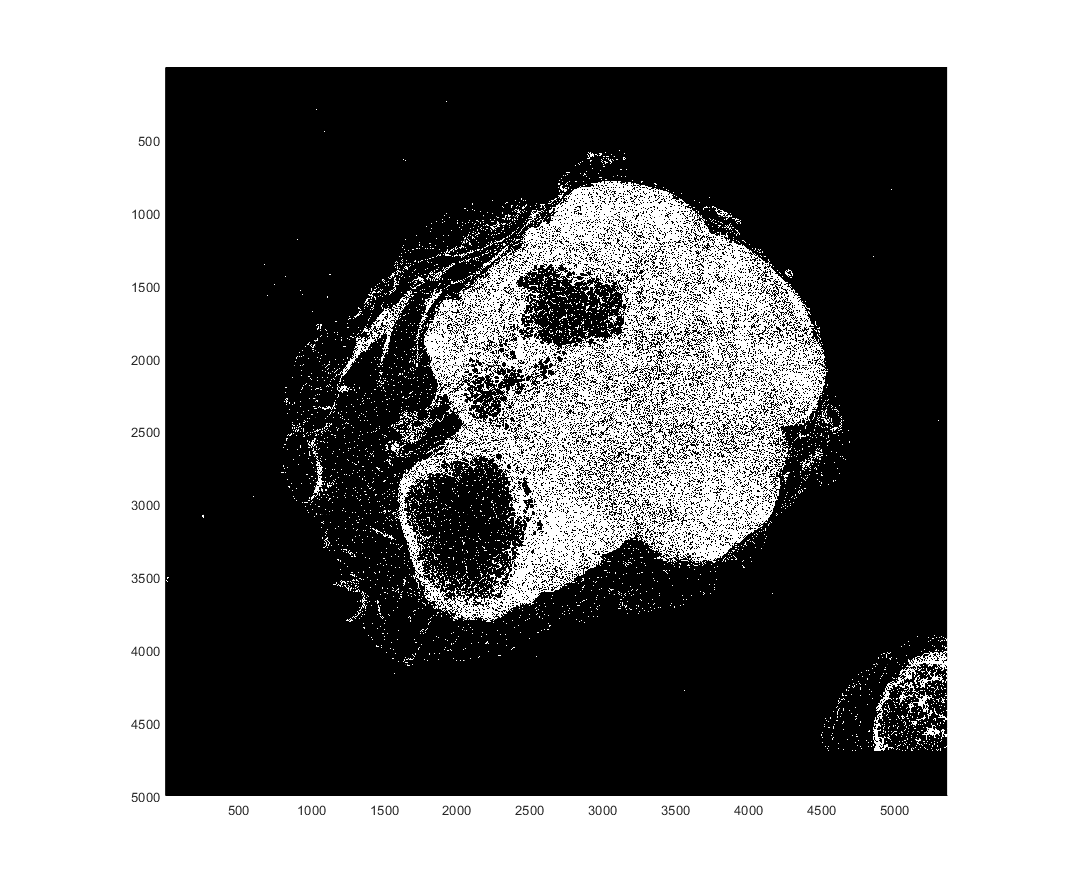

bigimageshow(bq,'CDataMapping','scaled');

Подтвердите на полном блокированном изображении и отобразите результаты.

bq = apply(bim, ... @(bs)~imbinarize(rgb2gray(bs.Data),thresh)); bigimageshow(bq,'CDataMapping','scaled');